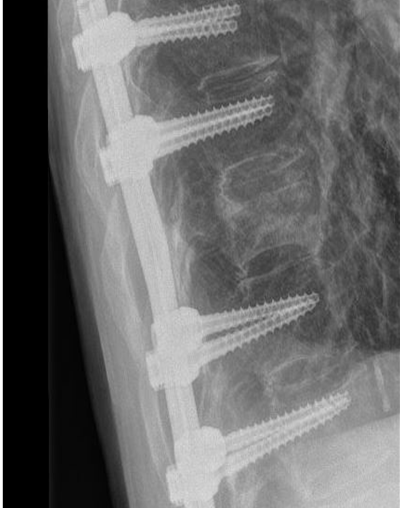

Bij een instabiele breuk is dit risico wel aanwezig en daarom is een stabiliserende operatie noodzakelijk. De revalidatie zal grotendeels overeenkomen met de revalidatie na een stabiele breuk zonder operatie.

Controle polikliniek

Na 6 weken komt u voor controle in de polikliniek bij uw behandelend arts. Er wordt een röntgenfoto gemaakt van uw rug en de voortgang van het herstel wordt beoordeeld. U krijgt advies over de opbouw van de oefeningen en hoe om te gaan met uw rug tijdens dagelijkse

activiteiten, werk en sport. Het advies is om de coördinatie en de kracht van uw rugspieren, buik- en flankspieren te trainen. Meestal wordt u hiervoor verwezen naar een fysiotherapeut.

Na 12 weken komt u voor controle in de polikliniek bij uw behandelend arts. Er wordt een röntgenfoto gemaakt van uw rug en de voortgang van het herstel wordt beoordeeld. U krijgt advies over de opbouw van de oefeningen en hoe om te gaan met uw rug tijdens dagelijkse activiteiten. Het advies is om de coördinatie en de kracht van uw rugspieren, buik- en flankspieren te trainen. Meestal wordt u hiervoor verwezen naar een fysiotherapeut.